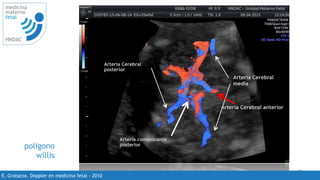

poligono

willis

Arteria Cerebral

media

Arteria Cerebral anterior

posterior

Arteria comunicante